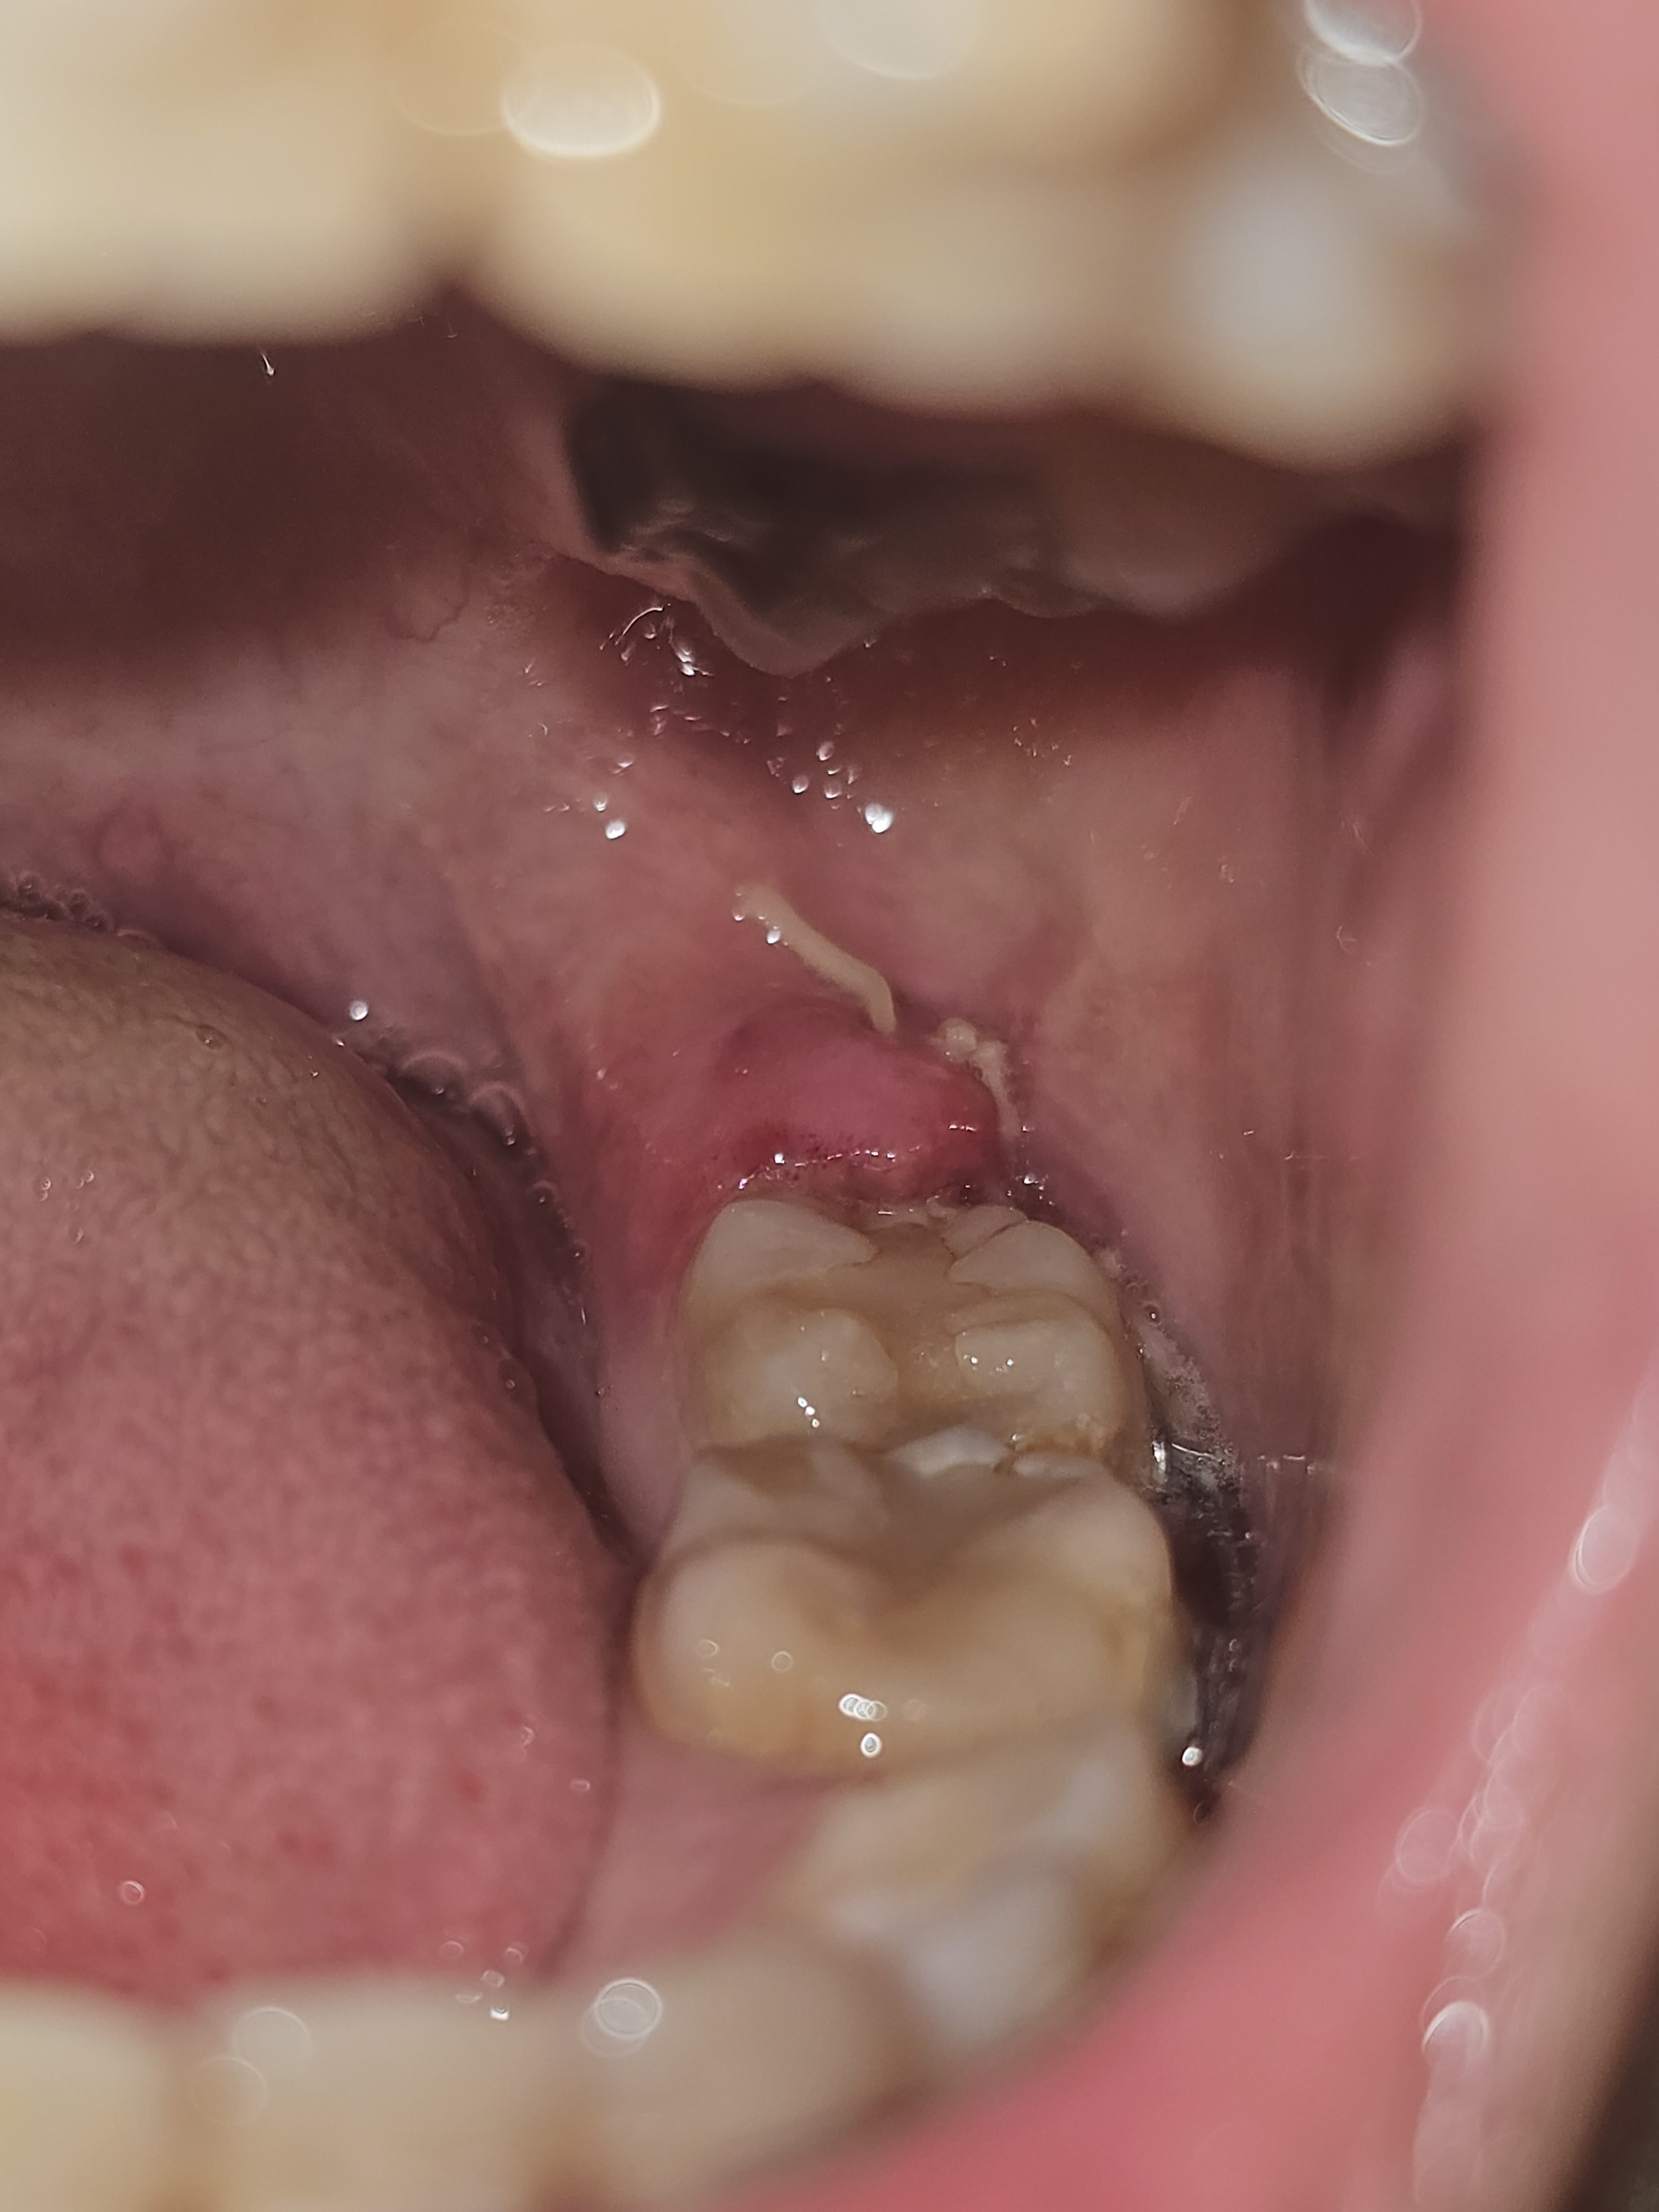

水平埋伏智歯の抜歯後、歯茎が腫れてチクチク、ズキズキと痛みます。

5/7(水)に左下の水平埋没智歯抜歯しました。

歯茎切開、骨切りを伴う、親知らずを3等分に割っての抜歯でした。

5/9(金)に歯ブラシで傷つけてしまったのか、10日の朝から抜歯箇所の歯茎が腫れ、強く痛みます。

11日(日)には痛みの範囲が広がりました。

12日(月)現在、痛みの強さは変わらずです。

※添付写真①は、5/11(日)朝に撮影したもの。

※添付写真②は、5/12(月)朝に撮影したもの。

痛みの種類は、超特大口内炎のようにチクチク、ズキズキします。

舌を動かすのも痛く、上の歯茎化膿箇所に触れるだけでも痛いので、会話や食事が辛いです。